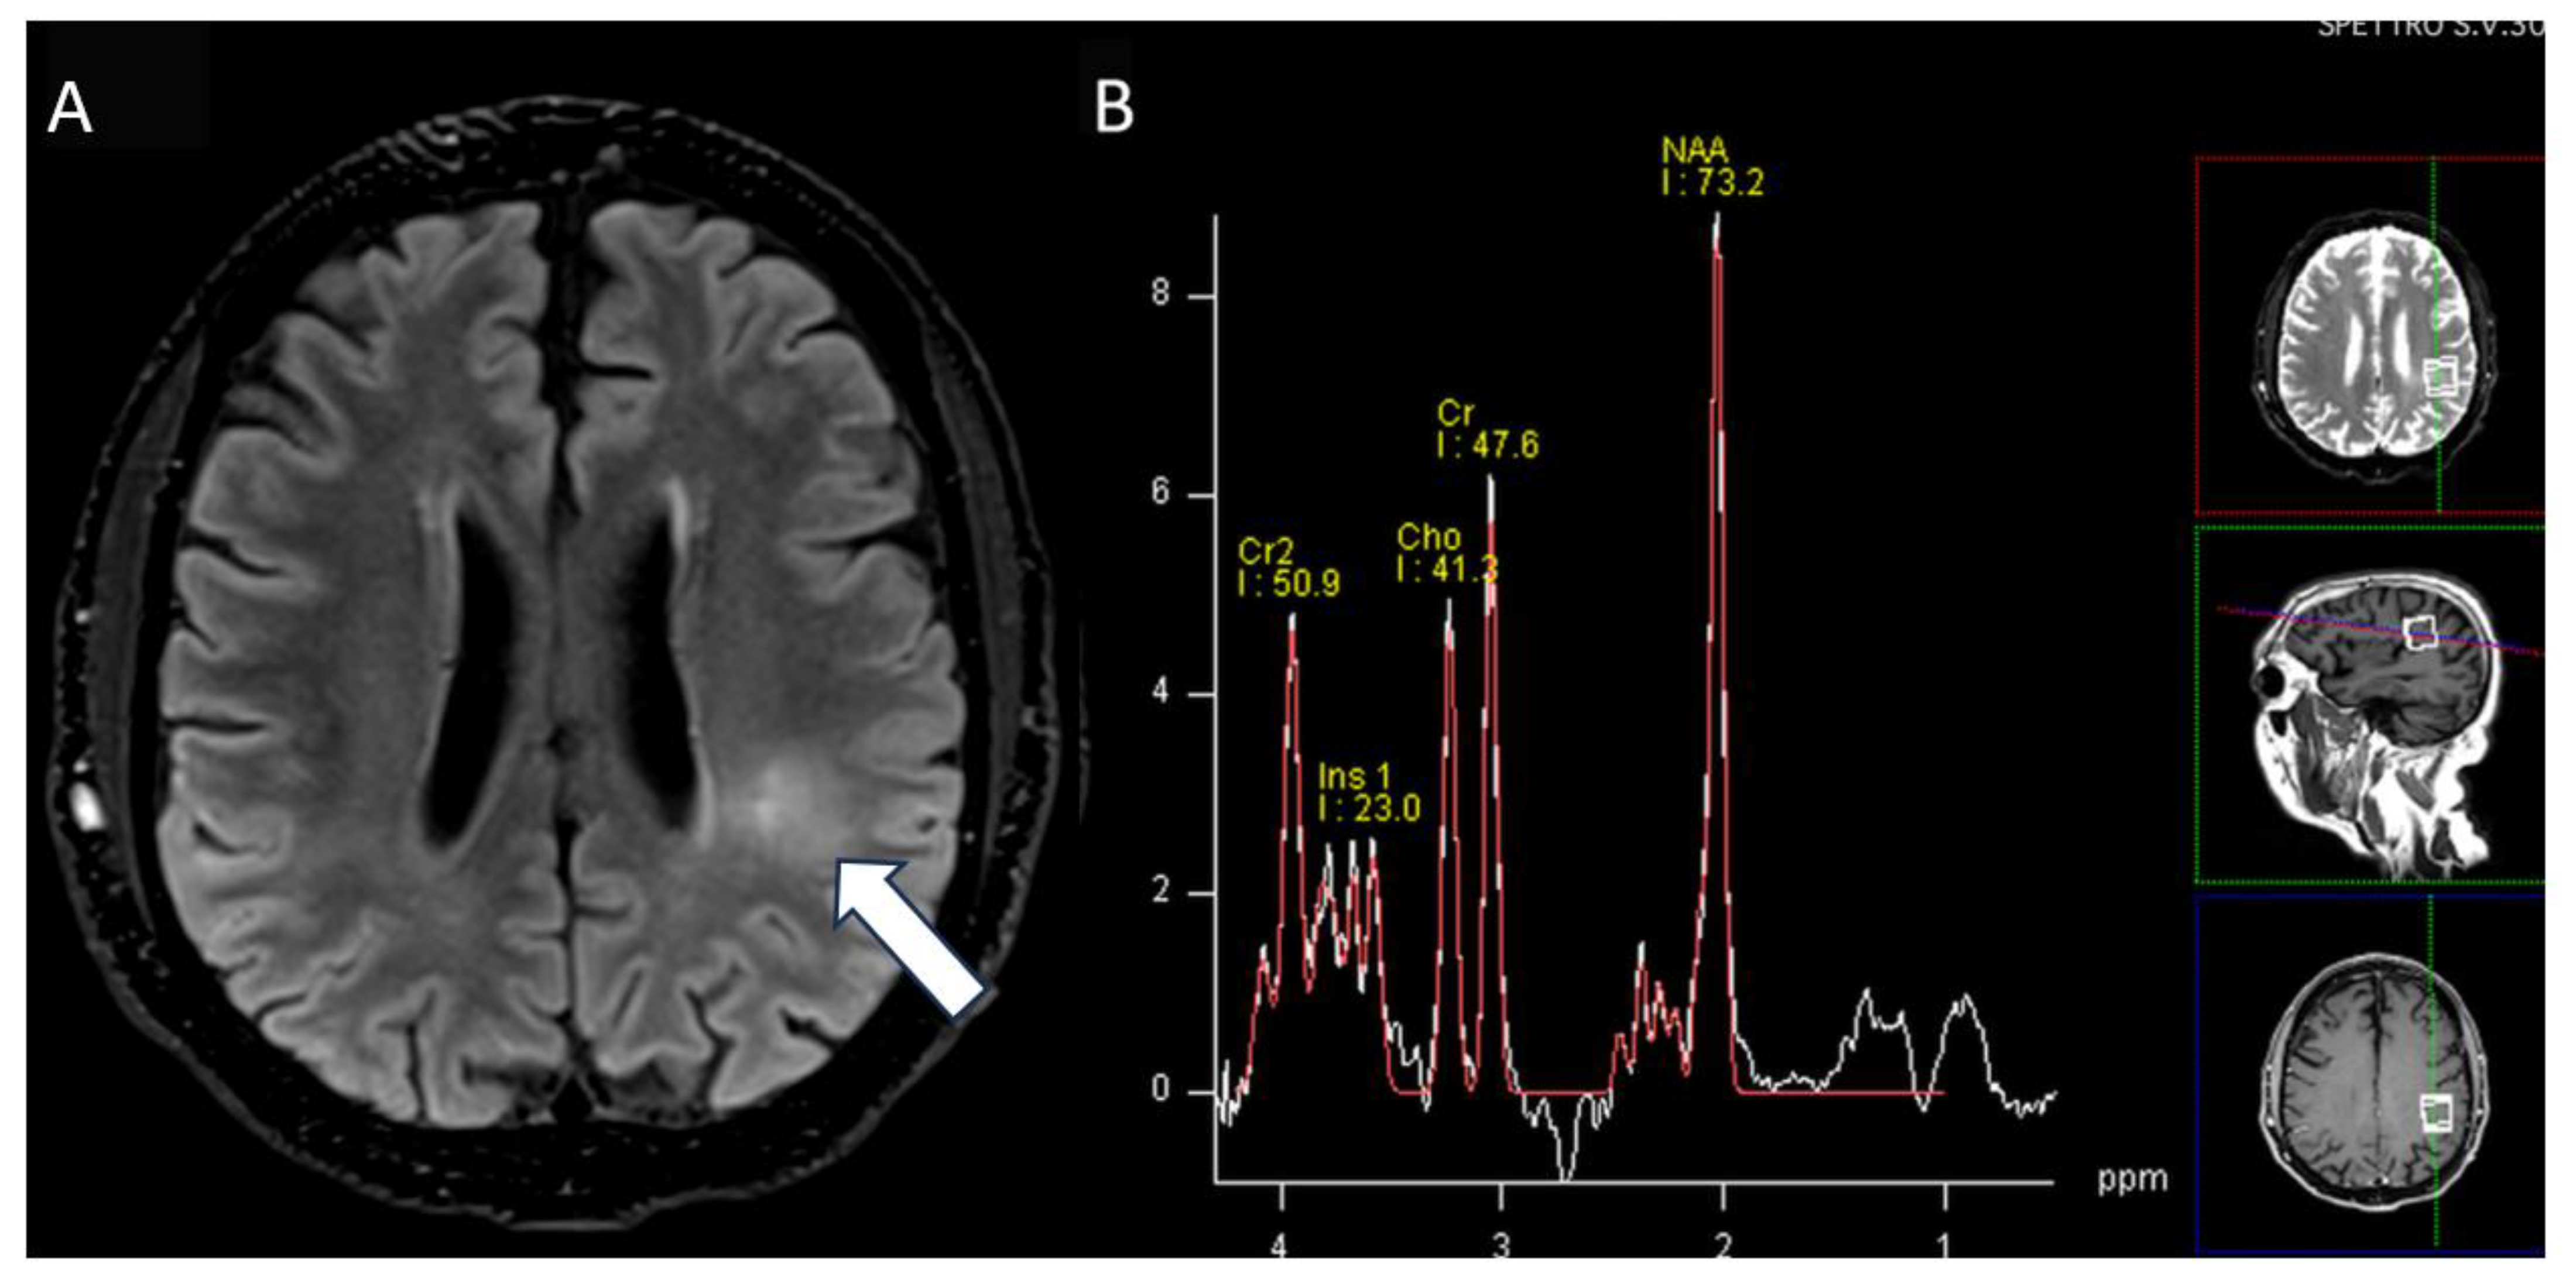

A 60-year-old Caucasian male presented with a secondary generalized focal motor seizure that caused post-ictal right hyposthenia, which resolved after 2 days. Neurological examination showed a slight leveling of the left lower limb during the Mingazzini maneuver, hyperelicitable osteotendinous reflexes in the four limbs with anisoreflexia left > right, pathological Babinski’s sign on the right, and hypopallesthesia of the lower limbs prevalent on the right with a cranio-caudal gradient. The patient had suffered from Waldenstrom macroglobulinemia 6 years before, but he recovered after treatment with Rituximab and Bendamustine. The patient did not have a history of epilepsy or any recent history of fever, vaccine, upper respiratory tract infection, abdominal symptoms, trauma, or travel. He suffered from psoriatic arthritis in treatment while taking Apremilast (300 mg × 2/day). At the time of presentation, the routine blood tests were unremarkable except for a slight increase in erythrocyte sedimentation rate (21 mm/h), lymphocytopenia (0.9 × 102/μL), and thrombocytopenia (127 × 103 μL). An unenhanced brain CT scan at the clinical onset revealed faint hyperdensity in some left parietal subarachnoid spaces (SHSs), which replaced the physiological hypodensity of the liquor (Figure 1). Patients underwent MRI scan after 5 days that revealed pathological signal and leptomeningeal enhancement on both left and right parietal SHSs without diffusion restriction (Figure 2). Further MRI examination performed one week later was negative for spinal cord and radicular/cauda equina alterations (Figure 3) but confirmed the stability of leptomeningeal findings. Leptomeningeal contrast enhancement was suspected for leptomeningitis, post-ictal hyperemia, and metastasis. After 20 days, the patient also underwent a total body CT scan to exclude any primary malignancies. Peripheral blood tumor marker (CEA, aFP, CA19-9, CA125, TPA, PSA, NSE, CYFRA), infective (HSV, HZV, JVC, EBV), and autoimmunity (anti-dsDNA, anti-RNP, anti-Sm) tests were negative. More than one month after the onset, cerebrospinal fluid (CSF) analysis documented the presence of monoclonal bands (light chain k, IgM) with elevated IgM index (0.45) calculated by [CSF IgM (mg/L)/serum IgM (g/L)]/[CSF albumin (mg/L)/serum albumin (g/L)] that is [1.89 (mg/L)/7.13 (g/L)]/[28.3 (mg/L)/48 (g/L)]. CSF flow cytometry revealed 2527 cells and 850 lymphocytes (33.64%). Among CSF lymphocytes, 87% of them were CD3+ CD5 +, while only 8% of them were CD19+ CD20+. The CSF tests did not reveal the presence of infectious meningitis (HSV1, HSV1, EBV, Adenovirus, Enterovirus, Parechovirus). The polymerase chain reaction test was negative for the L265P mutation in the MYD88 gene in both CSF and blood samples. CSF and MRI findings, along with the history of WM, were used to suggest the diagnosis of BNS within 2 months of the clinical onset (diagnostic timeline, Scheme 1). Therefore, brain tissue biopsy was not performed. A treatment with ibrutinib (140 mg three times daily) was initiated for the patient and is still receiving it. During a 1-year follow-up, there have been no new neurological signs or symptoms. The latest brain MRI showed a new subcortical left parietal lesion (18 mm) that was suspected to be caused by neoplastic cells infiltrating white matter vessels. Despite this, the spectroscopy map did not reveal any abnormal metabolic peaks in the lesion (Figure 4). The patient accepted the diagnosis and started and followed the therapy correctly. Despite his thrombocytopenia worsening, he tolerated the treatment well.

Figure 4. MRI axial images: (A) fluid-attenuated inversion recovery (FLAIR) image shows subcortical white matter hyperintensity on left parietal region (arrow) without abnormal peaks on single-voxel spectroscopy map (B).